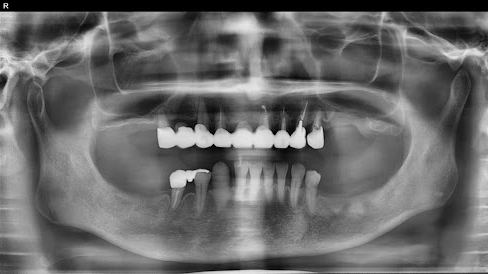

Before

枚方市のインプラントの症例

After

M・I 様 女性 70代

症状としては、左下56は、歯周病で欠損したと考えられるが、かなりの骨欠損をともなっていた。左上456に関しては、動揺が大きく、炎症が起き、排膿、および、歯性上顎洞炎を起こしていた。

治療法としては、動揺がひどくなってきて、炎症の症状もあったため、左上56の抜歯を希望。インプラント治療をその後、希望したため、左上4に関しては抜歯即時埋入。左上6に関しては、既存骨1から2mmでインプラント治療が厳しい状態であったが、グラフトレスサイナスリフトを行い、治療期間5か月はかかるということを説明して、インプラント埋入をおこないました。その後、2か月半後、大幅に骨が欠損している下顎56に対して、ショートインプラントを使用して、下顎神経の損傷を避けて、インプラント埋入を終えています。その後2か月後に光学印象で印象を行い、上顎刺億456歯、3ユニットのジルコニアブリッジを装着。下顎左側56に関しては、骨欠損が大きいため、歯冠長がだいぶ長くなるため、ジルコニアの連結冠を装着して治療を終えた。

治療結果は、上顎6に関しては、既存骨が少なく、厳しい治療ではありましたが、5か月で治療を終え、患者様の負担を最小限に抑えるができたと考えます。(従来のサイナスリフトでは、このようなケースでは1年以上、1年程度の治療期間がかかるか、治療が不可能と言われるケースだと考えます。)また、下顎は骨欠損が大きく、下歯槽管のリスクが起きることが考えられますが、ショートインプラントを使用することで安全に治療を行うことができました。

治療の期間・回数:治療期間5か月(上顎456 3ピースブリッジの治療は5か月(上顎既存骨が2mm程度しかなく、骨結合に時間がかかるケースであったために、5か月の治療期間が必要であった。)(左下56に関しては2か月半で治療を終えています。)治療回数は、13回。

治療の価格:1,474,000円(税込)

治療費の内訳:左上46および左下56のインプラント基本料(フィックスチャー及び手術費用、投薬費用、レントゲン費用、インプラント上部費用(アバットメントおよびジルコニアクラウンの費用用)330000円(税込み)×4本分 1320000円(税込)。左上5ジルコニアポンテック費用88000円(税込)。オプション費用、左上4抜歯即時埋入加算(人工骨費用を含む)+グラフトレスサイナスリフト費用 33000円(税込)、左上6グラフトレスサイナスリフト費用 33000円(税込)

治療のリスクや副作用:手術後に、痛みや腫れ、出血、合併症などを引き起こす可能性があります。噛む感覚がご自身の歯と異なる場合があります。見た目がご自身の歯と異なる場合があります。手術後にメインテナンスを継続しないと、インプラントが抜け落ちる可能性があります。